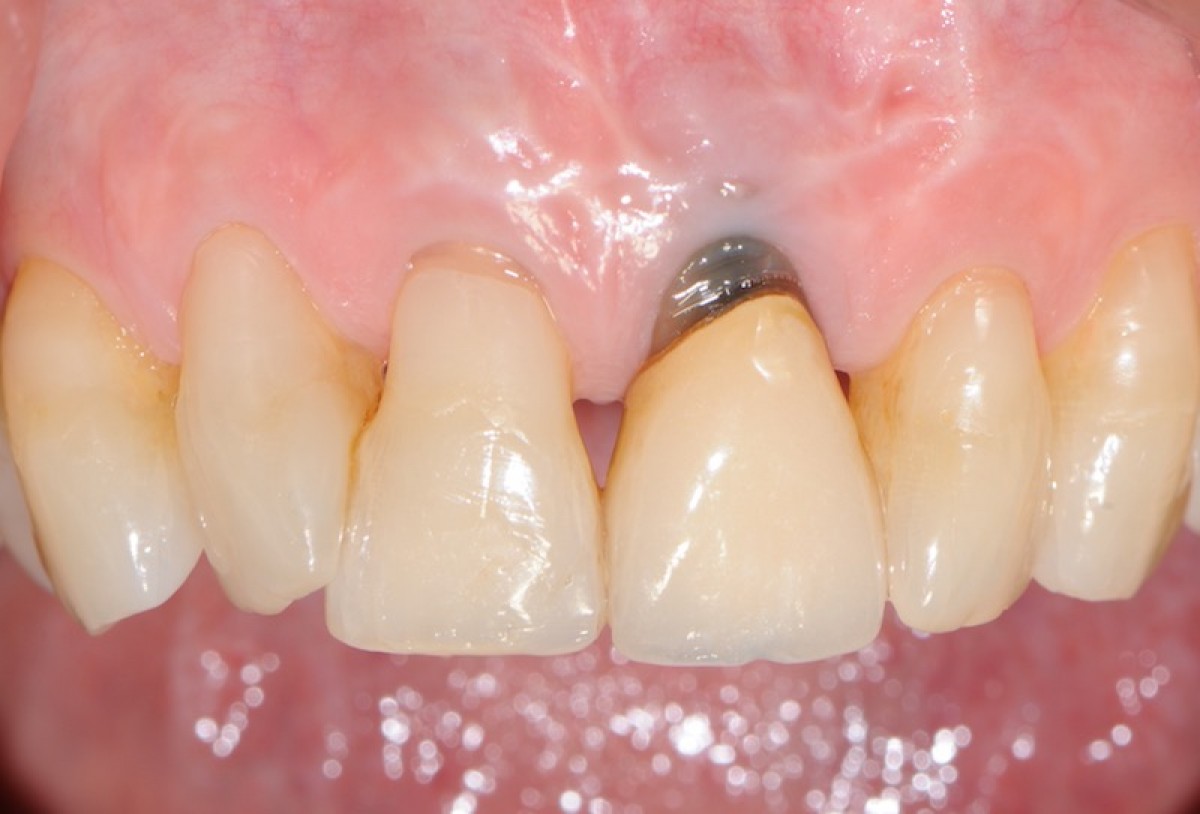

The objective of this prospective cohort study is to test the performance of a new xenogenic collagen matrix as a socket sealing material, to allow second-intention healing of post-extractive sockets filled with a xenogenic bone substitute or with an immediate submerged implant.

10 patients were recruited, presenting a single-rooted tooth scheduled for extraction. After atraumatic tooth removal, the post-extractive alveolus received either a socket preservation procedure or an immediate submerged implant. In both cases, the gingival margins of the alveolus were sealed with a xenogenic collagen matrix (Mucoderm, Botiss Dental, Zossen, Germany). The following parameters were evaluated:

• exposed surface of the matrix at the end of surgery (T0);

• soft tissue healing at 1, 4, 6, and 8 weeks from surgery (T1-4);

• histological aspect of gingiva samples, harvested 20 weeks after surgery (T5);

• aesthetic performance provided by the socket sealing material (T4).

• the mean post-operative exposure area of the matrix was 26.25 mm2 (14.2 to 38.84 mm2 );

• 8 weeks after surgery, full wound closure was achieved in 9 out of 10 sites with healthy keratinized tissue;

• the mean colorimetric score ∆E between the regenerated site and the surrounding gingiva was 3.76 (3 to 6.55).

Seven out of 10 patients reported an excellent aesthetic integration of the matrix (∆E < 3.7).